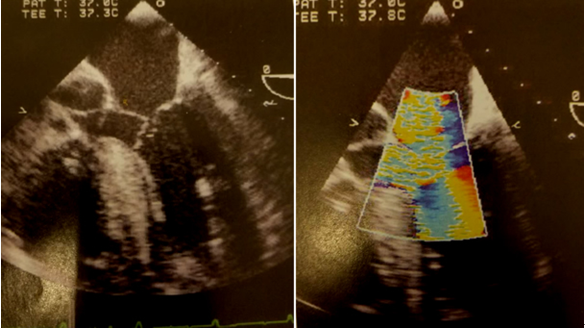

提示窦性心律,多导联ST段抬高,提示广泛前壁心肌梗死。该患者入院后收住CICU,但体征仍不稳定,呈休克貌,床边原有去甲肾上腺素用量渐增大,最高约0.9μg•kg-1•min-1,血压仍难以维持,最低 81/43mmHg。此时经原发症状初始已有6h。经评估后患者无内科保守治疗指征,遂急诊在全身麻醉、非体外循环下行“开胸探查及心脏修补术”。术前麻醉常规于右侧颈内静脉植入漂浮导管一根, 此时测得心排达 6.1L/min,SVO2为51%,但经计算体循环阻力仅为760(dyne×sec)/cm5。术中开胸见心包内实无明显血液积存, 但心肌肿胀剧烈, 打开心包后见心脏呈整体扩张、 肿胀样改变。左室活动较差,见单矛引流软管刺入心脏左室表面, 局部破裂,心脏伤口表面仍见新发出血(图2)。取用约3×3cm 自体心包补片沿伤口外周连续缝合,将心脏表面穿刺点破损处局部修补加以止血。此后原拟关胸, 但在合拢胸骨时血压波动异常, 反复有快速室性心律失常发生,心率170-180次/min,经食道超声(TEE)证实其存SAM (systolic anterior motion)征(图3),快速补充血浆,使用少量β受体阻滞剂静脉注射,减低血管活性药物用量后缓解, 但此时心肌仍较为肿胀,遂延迟关胸。并将左西孟旦

图3 术中经食道超声证实SAM征表现